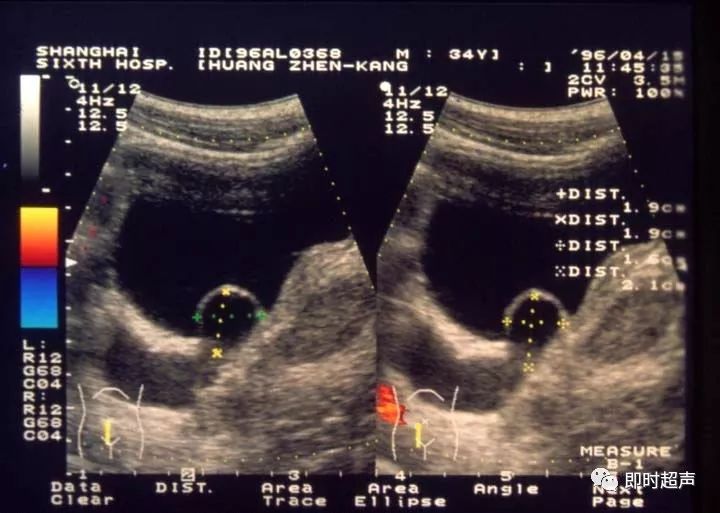

图4-1-3 肾积水声像图 调色碟型

轻度肾积水,在声像图上出现肾窦分离,肾盂肾盏均有轻度积水,但肾实质厚度和彩色血流不受影响。中度肾积水,肾窦回声中出现无回声区,因各人肾盂肾盏原来形态不同,显示各种形态的肾积水声像图,肾盏积水明显可见(图4-1-3~图4-1-5)。重度肾积水,肾盂肾盏明显扩大,显示各形无回声区,肾实质明显变薄,肾实质内彩色血流明显减少或消失。